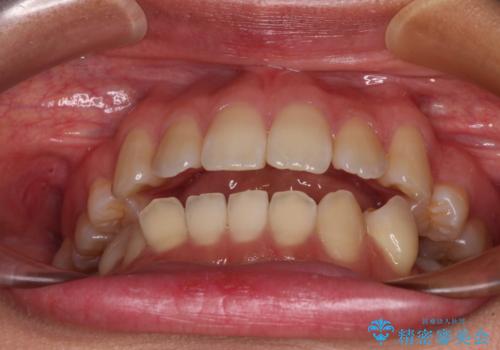

- 上下顎前歯部の非接触(開咬)と下顎のデコボコを主訴に来院された患者様です。

右側上下と左上の小臼歯が一本ずつ少なく、さらに骨格的な左右差もあり上下の真ん中の位置がずれています。

下顎のデコボコの解消と、真ん中の位置を改善するために左下の小臼歯を抜歯することとしました。

また、開咬を改善するため臼歯部にアンカースクリューを用いて圧下する力をかけていきました。

舌を突出する癖があり、それにより開咬が悪化したり、後戻りの原因になるため、舌のトレーニング(MFT)も行いました。